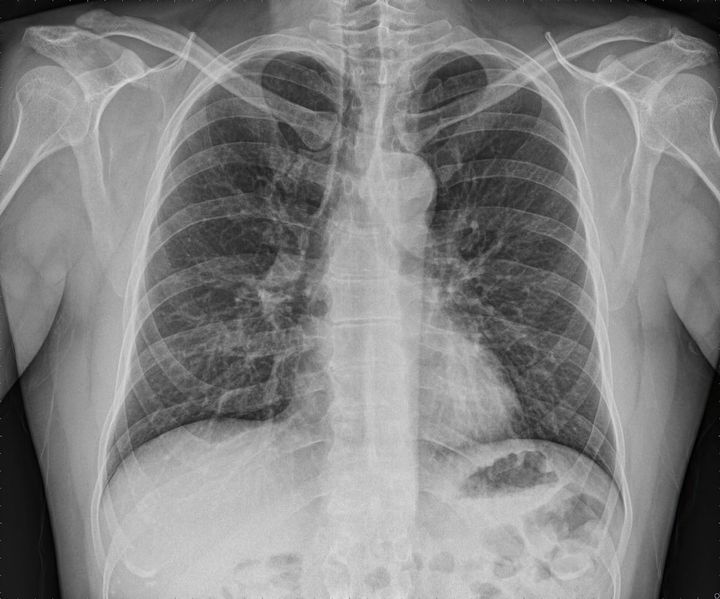

肺のレントゲン写真

※写真はイメージです